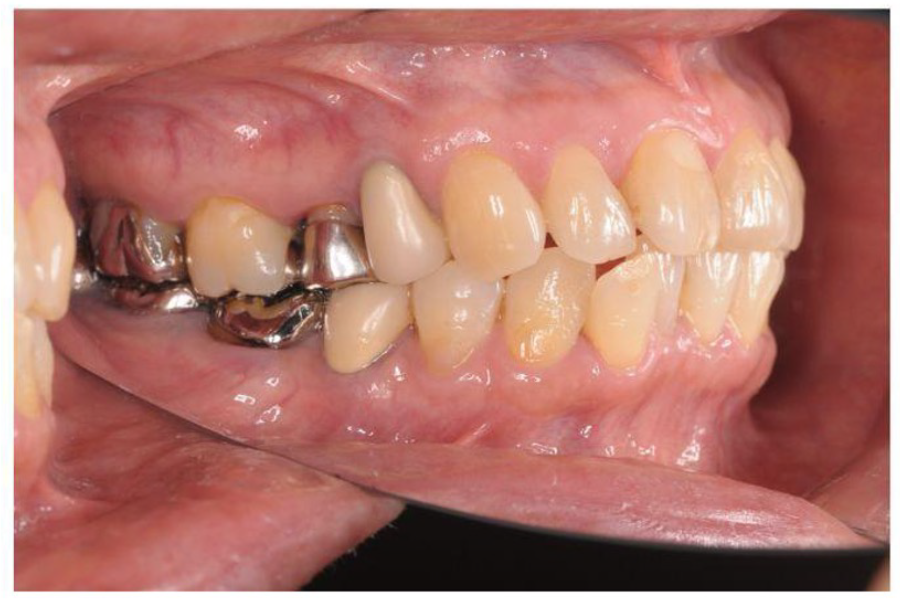

治療前